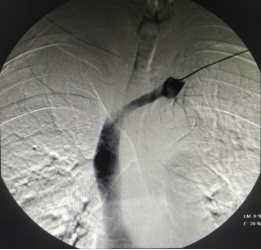

DSA下行血管造影及内瘘PTA手术过程

01. 动静脉内瘘PTA术

吴某某 男 57岁,尿毒症透析患者,左前臂自体动静脉内瘘,血流量不足150ml/min,不能满足透析需要。

一般情况下,内瘘流量不足多为血管内狭窄或血栓形成导致,将形似“气球”的球囊扩张导管放到血管腔内狭窄或血栓部位,给予一定压力注入液体后扩张病变部位,血管通畅,术后就可以穿刺透析了。这种微创手术相对传统开刀手术而言,最大限度保留血管资源,减少手术创伤。